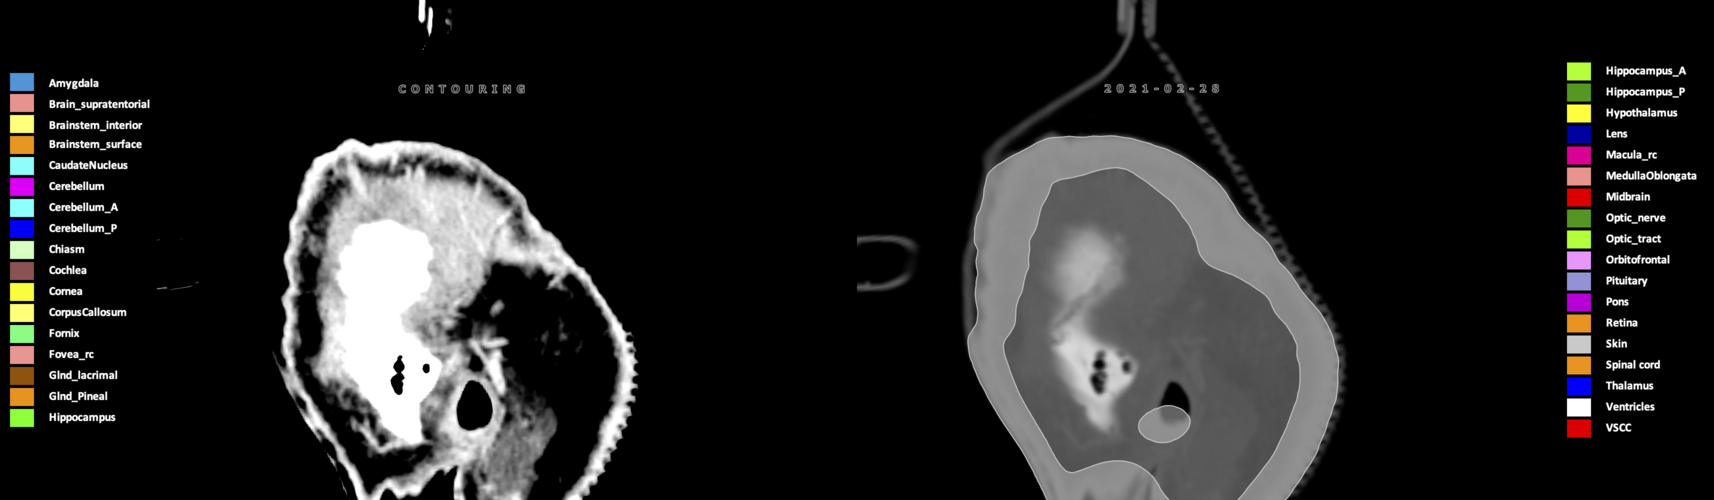

Three-dimensional delineation of the 25 consensus OARs for neuro-oncology are shown on CT (WW/WL 120/40, 3000/600), 3T MR images, (T1Gd, T2FLAIR 1mm) and 7T MR (MP2RAGE 0.7 mm). All are presented in transversal, sagittal and coronal view.

Included are all OARs known to be relevant for radiation-induced toxicity in neuro-oncology: brain, brainstem (midbrain, pons, medulla oblongata), chiasm, cerebellum (anterior & posterior), cochlea, cornea, hippocampus (anterior & posterior), hypothalamus, lens, lacrimal gland, optic nerve, pituitary, skin, and vestibular & semicircular canals. To further facilitate research on cognition, vision and radiological changes after irradiation of the brain, potential clinically-relevant OARs are included: amygdala, caudate nucleus, cerebellum (anterior & posterior), corpus callosum, fornix, macula, optic tract, orbitofrontal cortex, periventricular space (PVS), pineal gland, and thalamus.